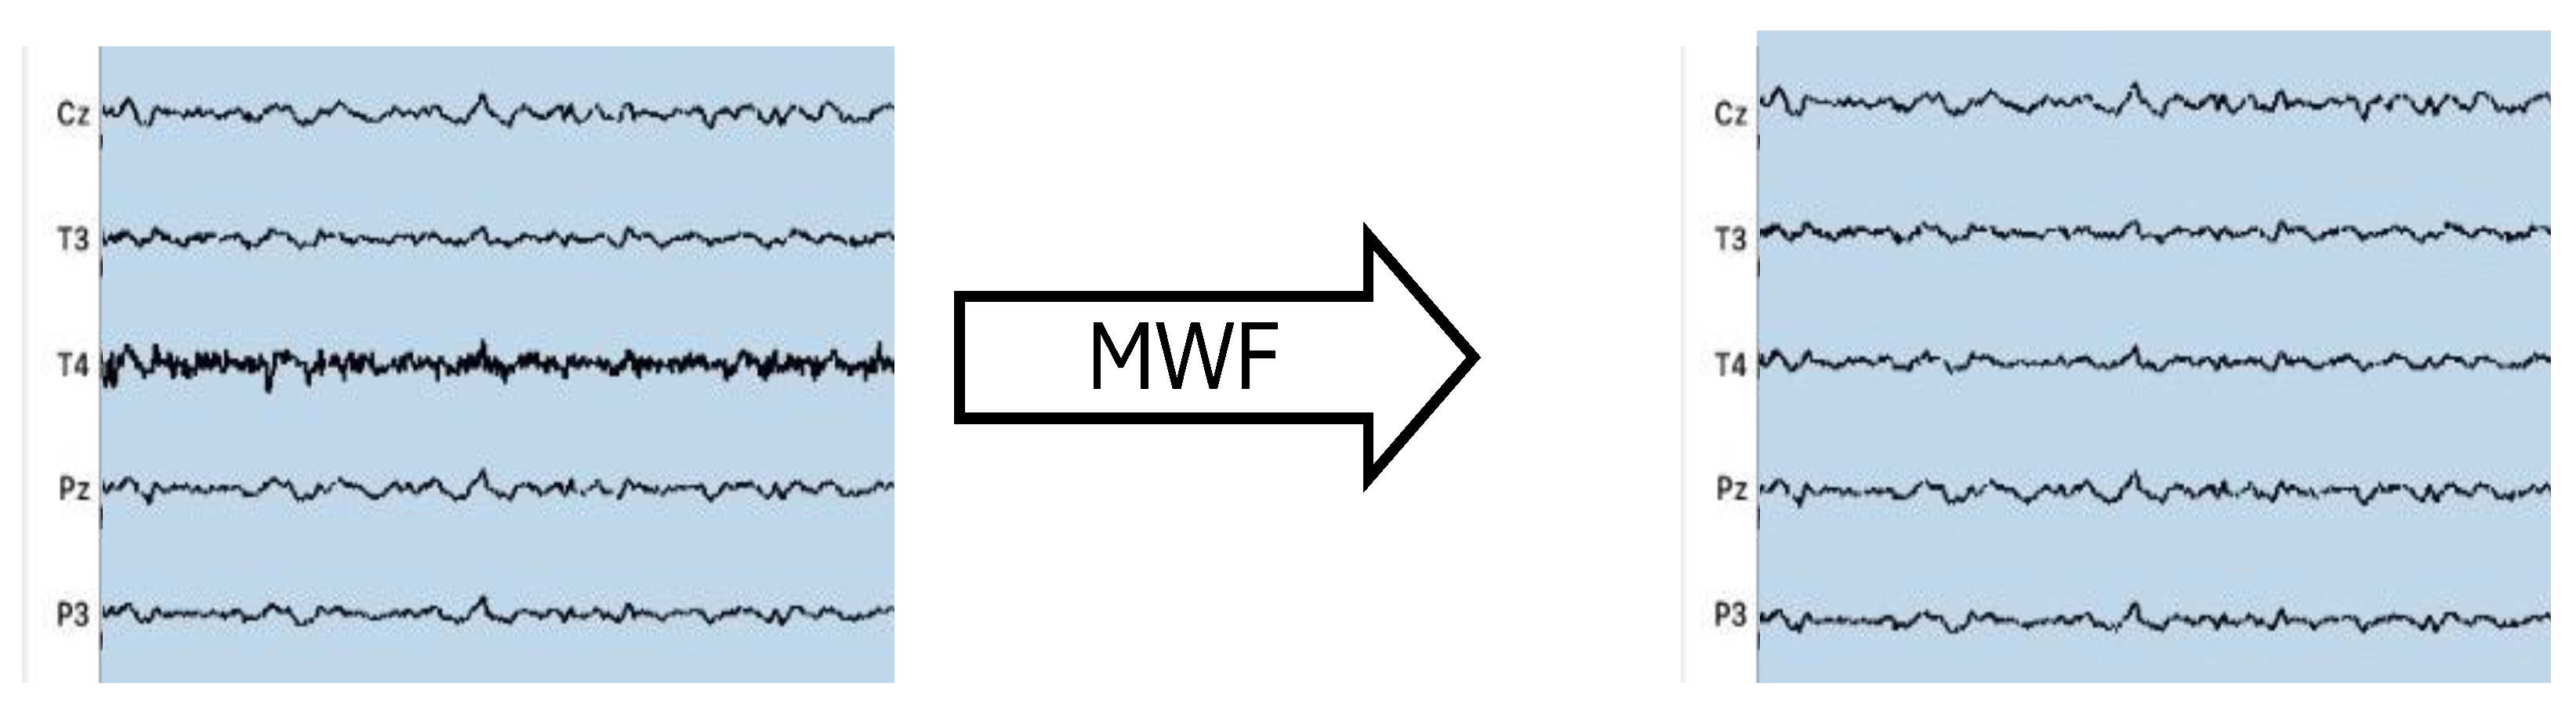

2.4. CI Artifact Removal

3.2. CI Artifact Reduction